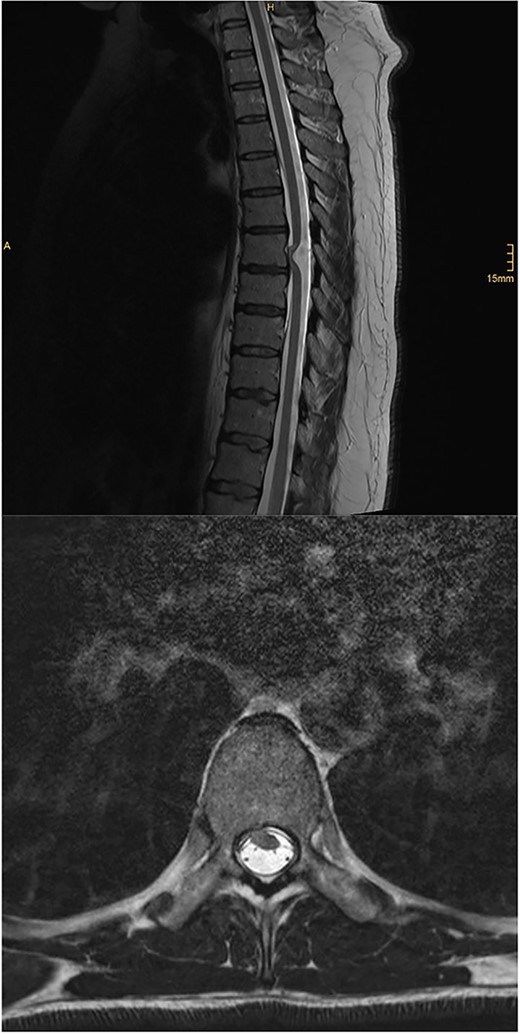

MRI of the brain (see Fig. 1) revealed features of low intracranial pressure. An MRI of the spine (see Fig. 2) revealed focal thoracic herniation of the ventral cord through the thecal sac with CSF signal in the anterior epidural space. No cord signal abnormality was demonstrated. Neurological examination was unremarkable with no numbness or weakness of the lower limbs.

Illustrative sagittal and axial T2 MRI of the spine demonstrating ventral SCH; there is focal anterior displacement of the spinal cord out of the dural sac through a dural defect at the T7 level; unlike in the present case, these images demonstrate an ill-defined focus of T2 hyperintensity within the cord at the T7 level; case courtesy of Kamran Hajiyev, from the case rID: 76419 (https://radiopaedia.org/cases/76419?lang=gb)